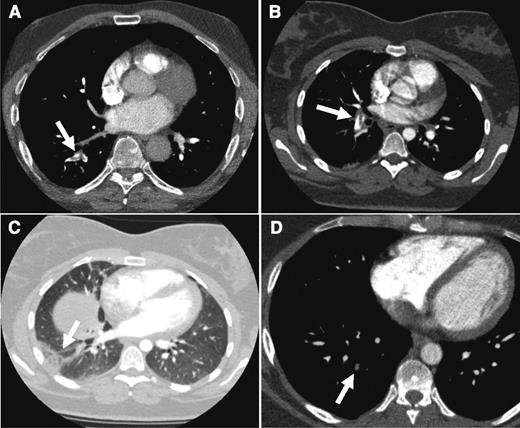

CTPA results from the cases. CTPA of patients from case 1 (A: arrow indicates acute thrombus in segmental artery to the right lower lobe), case 2 (B: despite breathing artifacts, clear visualization of acute PE in right segmental artery; C: arrow shows a wedge-shaped peripheral consolidation indicative of pulmonary infarction), and case 3 (D: arrow points to an organizing mural thrombus in a right basal segmental pulmonary artery).

With this in mind, the patient was informed of the suspected PE and the potential risks of radiation exposure. She agreed to CTPA, which showed a large embolus in a right segmental pulmonary artery (Figure 2B). A wedge-shaped, pleural-based opacity in the right lower lobe indicated the concomitant presence of pulmonary infarction (Figure 2C).